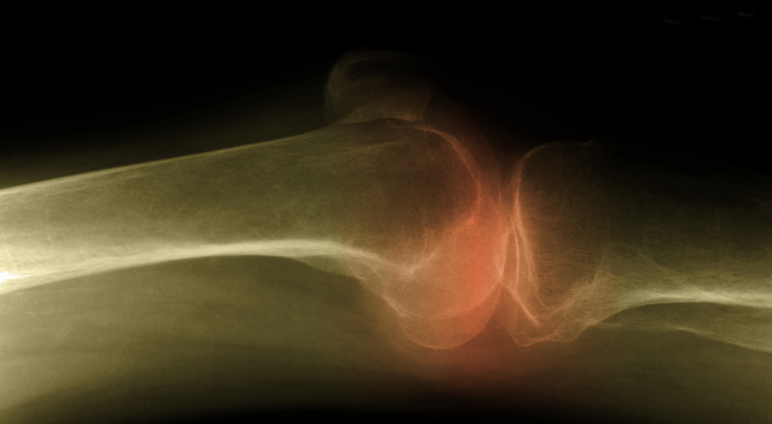

Alison is a 67-year-old woman with osteoporosis who takes daily calcium supplements and exercises 5 days a week. Because she has high levels of homocysteine in her blood, you recommend that she also add...